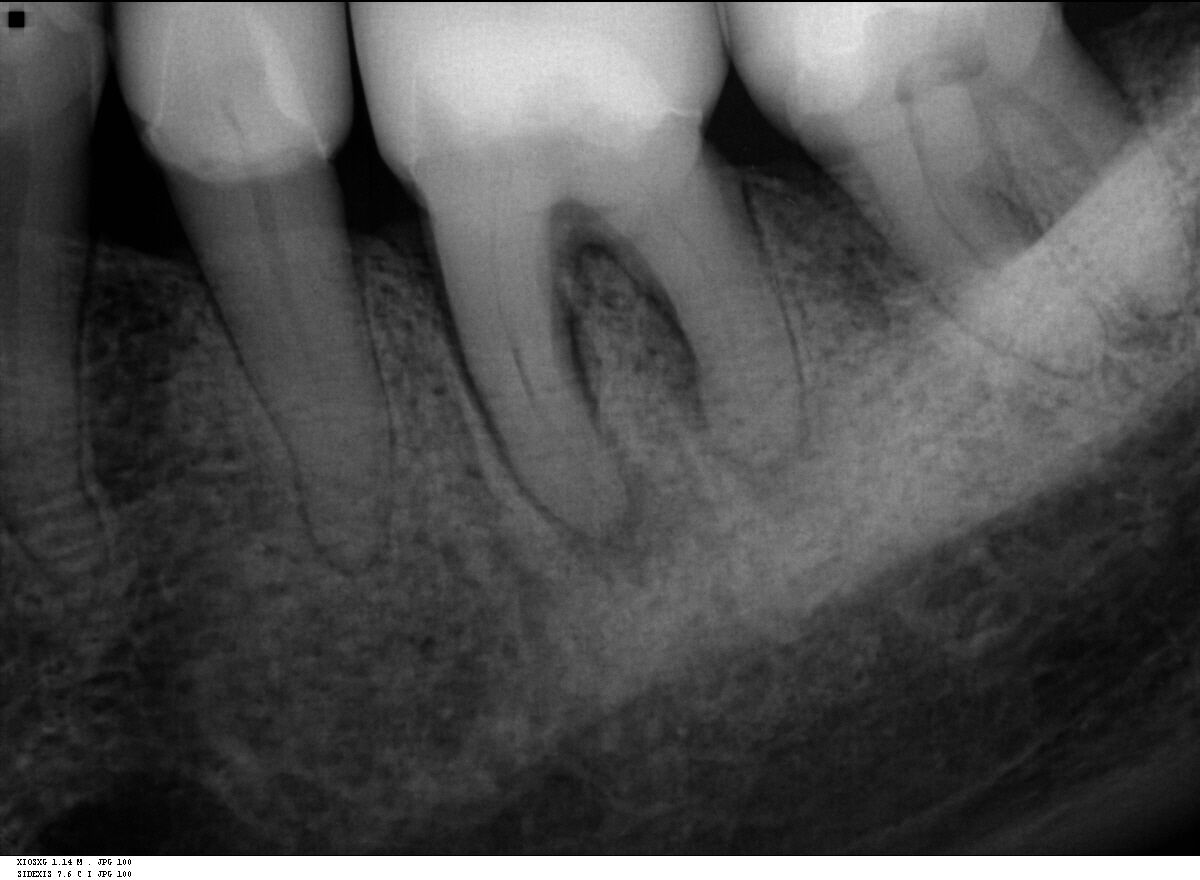

Fall 1: Revisionsbehandlung

Ausgangssituation